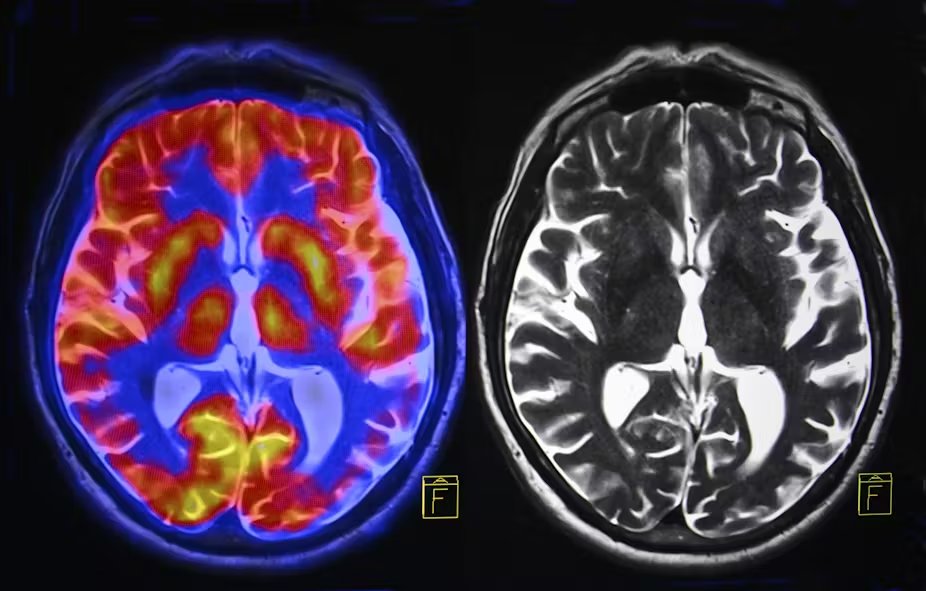

A VISUAL THREAD on what's real: 🧵 Image